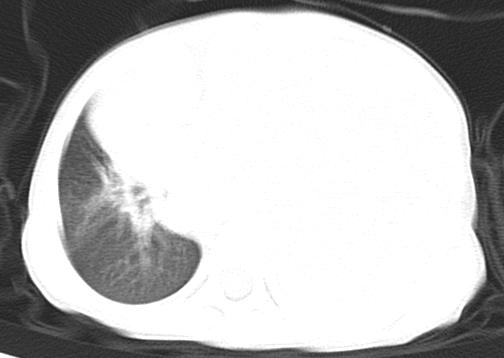

患儿 女 4岁,发热 咳嗽 胸透 考虑:左侧脓胸

左侧胸廓内见大量密实阴影,肺尖部尚有少量肺组织影,纵膈明显受压移位,肋骨未见明显受侵征象,虽然病人年龄较小,但如此大量的“积液”,还是要警惕,不同意一般感染,可结合穿刺脱落细胞学检查。

1)考虑左肺炎症感染。2)左侧大量胸腔积液。

1)考虑左肺炎症感染。2)未经穿刺只能定左侧大量胸腔积液。

左侧张力性大量胸腔积液压迫性肺不张、感染;建议治疗后复查。